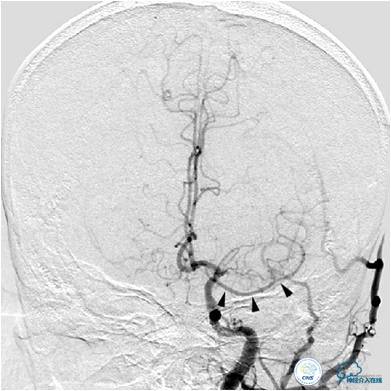

患者入院后,完善颅内CTA(图1)及血管造影(图2~3)检查,发现右侧颈内动脉颅内段闭塞,右侧大脑前动脉依靠左侧颈内动脉系统通过前交通动脉供血,右侧大脑中动脉供血区则依赖于右侧大脑前动脉(ACA)软脑膜代偿供血,左侧大脑中动脉闭塞,依靠一少见血管代偿供血,该血管起自左侧大脑前动脉A2段起始部,代偿供应左侧大脑中动脉供血区。由于该患者灌注CT(图4)未见明显低灌注区,遂给予患者抗血小板、降脂及控制危险因素治疗出院。出院后电话随访未再出现过上述症状。

图2:患者右侧颈内动脉造影提示右侧大脑中动脉次全闭塞,血流缓慢。大脑前动脉未见显影。

图3A:左侧颈总动脉造影动脉期,看到异常血管代偿供应左侧大脑中动脉分布区(箭头),双侧大脑前动脉双干显示。

图3B:左侧颈内动脉造影动脉晚期提示双侧大脑半球染色尚可,右侧大脑中动脉供血区由右侧大脑前动脉的软脑膜动脉代偿。